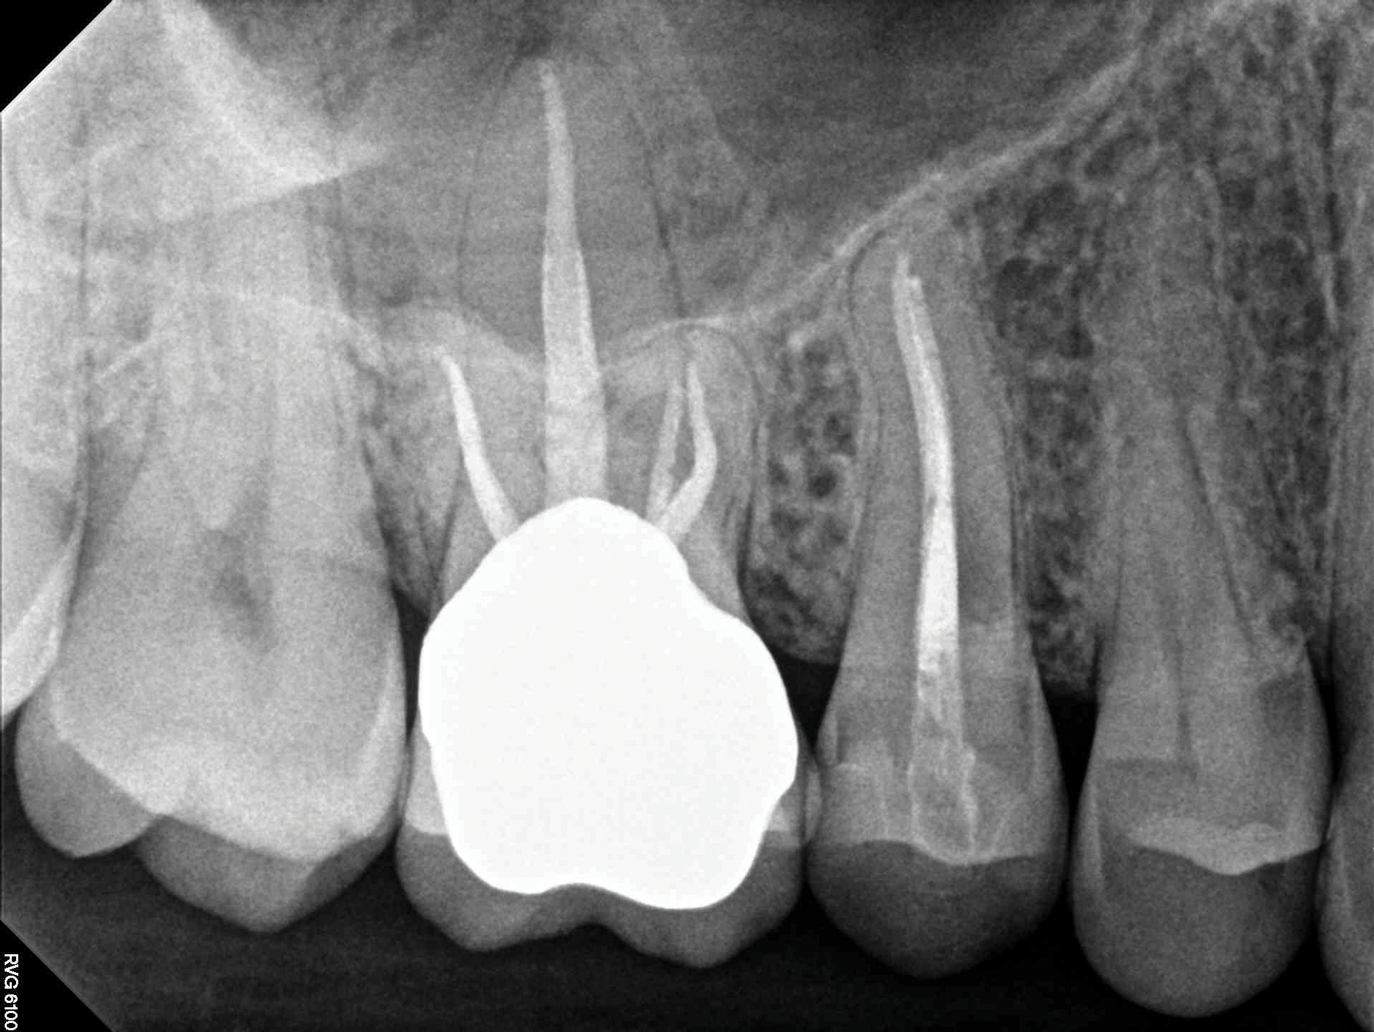

(1.) Preoperative CBCT scan showing Class 2 ECR defects on teeth Nos. 3 and 4 that were surgically accessible.

Figure 1

(2.) NSRCT, which had previously been completed on tooth No. 3, was also completed on tooth No. 4 prior to initiating surgical repair of the ECR lesions because it exhibited signs and symptoms of irreversible pulpitis.

Figure 2

If an ECR lesion is surgically accessible, external repair with gingival flap surgery is the treatment of choice (Figure 1 through Figure 6). When considering external repair, clinicians should evaluate each case for potential postoperative esthetic concerns, such as the possibility of recession following surgical repair.6,7 Moreover, clinicians should assess the overall restorability of affected teeth because the surgical repair of large ECR lesions may predispose them to fracture.6 When a Heithersay Class 1 lesion is diagnosed, nonsurgical root canal therapy (NSRCT) in addition to the surgical repair is often unnecessary. However, in Heithersay Class 2 or larger defects where pulpal involvement is suspected or confirmed, NSRCT may be necessary in addition to surgical repair.6 If NSRCT is indicated in addition to surgical repair, it is recommended that it be completed prior to surgery to avoid exacerbating pulpal disease.